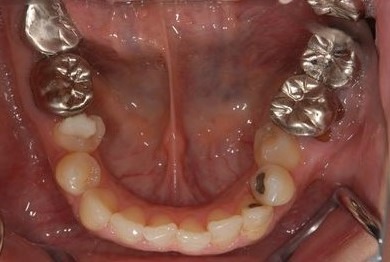

| 性別/年齢 | 女性 / 38歳 | ||||||||||||||||||||||||||||||||

| 主訴 | 奥歯の痛み(虫歯)。銀歯の所だと思います。なるべく痛くない治療がいいです。 | ||||||||||||||||||||||||||||||||

| 治療方針 | セラミック治療にて、審美的回復を行う。 | ||||||||||||||||||||||||||||||||

| 治療内容 | ハイブリッドセラミッククラウン1本(ハイブリッドセラミック用土台1本) | ||||||||||||||||||||||||||||||||

| 総治療費 | 96,600円 | ||||||||||||||||||||||||||||||||

| 治療期間 | 2ヶ月 |